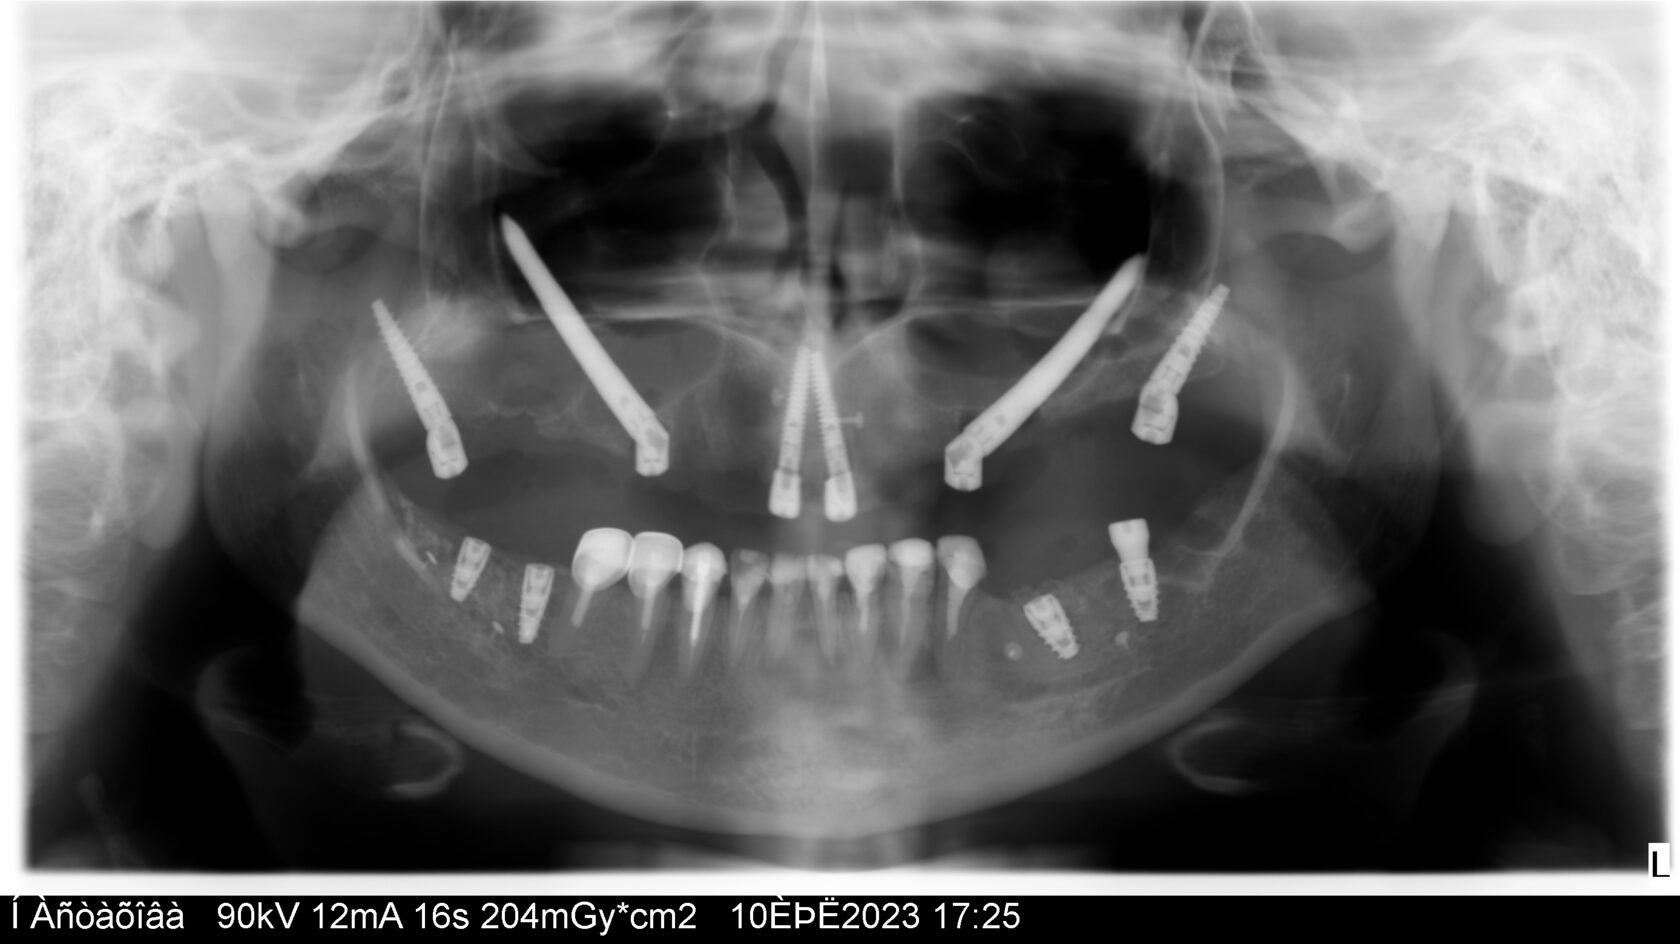

Цифровые протоколы немедленной нагрузки с экстремальной степенью атрофии

Анатомические особенности верхнечелюстной и скуловой костей Особенности проведения седации Оценка компьютерной томографии и визуализирующий исследования, начальное планирование Обоснования ZAGA протокола

От 4 до 6 имплантатов (Maxila on4/ on 5/ on 6) Длинные имплантаты (небный и транссинусальный подход) Скуловые, птеригоидные, назальные имплантаты (транссинусальная, трансназальная постановка)

Разбор Free hands протоколов- итальянская техника от JDental Care! Насо - палатинальная постановка Трансинусальная постановка с фрезами JDNasal Трансназальная постановка с фрезами JDNasal по протоколу Nasa consept Протокол установки скуловых имплантатов anterior/posterior zygomatic по протоколу Zaga concept Трансинусальная и стандартная постановка птеригоидного имплантата Paga Concept